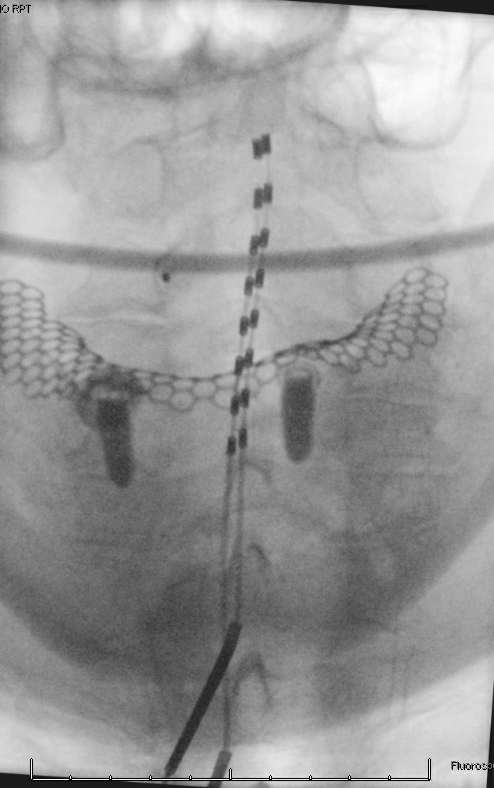

Cervical SCS for post-herpetic neuralgia in the V1 distribution by targeting nucleus caudalis. Thank you, Shervin, for your guidance. It is always a pleasure to work with my mentee — Dr. Gill. @rshervin @benjamin_gill @UofUtahPain